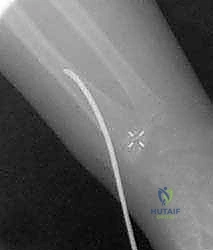

1. تقنية المسامير النخاعية المرنة (Métaizeau Technique / TENs)

تُعد هذه التقنية ثورة في جراحة عظام الأطفال، والأستاذ الدكتور هطيف من رواد تطبيقها في اليمن.

* الفكرة: بدلاً من فتح المرفق، يتم إجراء شق صغير جداً (لا يتعدى 1 سم) عند منطقة الرسغ (أسفل الكعبرة).

* يتم إدخال مسمار تيتانيوم مرن (Titanium Elastic Nail) داخل التجويف النخاعي لعظم الكعبرة، ودفع المسمار للأعلى حتى يصل إلى منطقة الكسر في المرفق.

* يتم استخدام طرف المسمار المنحني كـ "أداة دفع" لرفع رأس الكعبرة المكسور وإعادته إلى مكانه التشريحي الصحيح بدقة متناهية تحت جهاز الأشعة (C-arm).

* المزايا: لا يوجد فتح جراحي في المرفق، الحفاظ التام على التروية الدموية، ندبة شبه معدومة، وسرعة فائقة في التعافي.

صورة توضح دخول المسمار المرن عبر التجويف النخاعي لرد الكسر من الداخل دون المساس بمفصل المرفق.